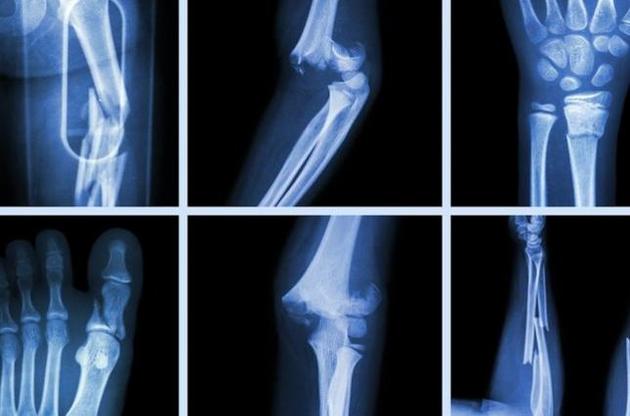

Датський стартап Particle3D розробив технологію друку пористих протезів з ортофосфата кальцію і готовий почати її тестування на людях найближчим часом. Як повідомляє "Популярная механика", ця технологія дозволяє не тільки створювати індивідуальні протези під кожного пацієнта, але і за кілька років відновити живу тканину скелета.

Створення протезів з ортофосфата кальцію в медицині не новинка. Але до цього протезистам фактично доводилося ліпити протез вручну. Нововведення ж датської компанії в тому, щоб друкувати пористі структури, аналогічні справжнім кісткам. У тілі пацієнта вони грають роль будівельних лісів, які організм використовує для відновлення власних тканин.

Для створення такого протеза необхідно провести сканування пошкодженого місця, завантажити отримані дані в систему автоматизованого проектування, внести корективи у отриману модель і відправити на друк.